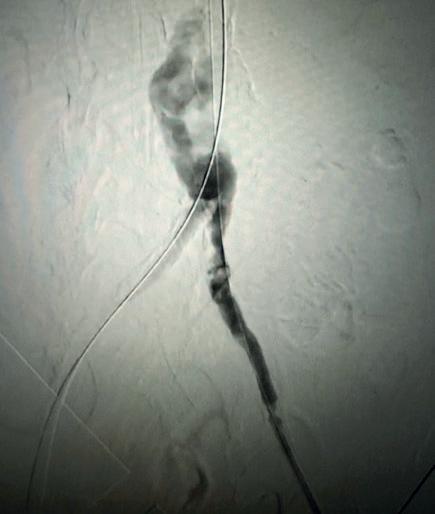

Case 1: The Shockwave L6 device in the setting of FEVAR and complex iliac stenosis

An 82-year-old man with a history of coronary artery disease (CAD), hypertension, hyperlipidemia, and peripheral arterial disease (PAD) presents with rest pain as well as

a large pararenal abdominal aortic aneurysm (AAA). His computed tomography angiography (CTA) revealed very dense and highly diseased iliac vessels with calcium deposition along most of the bilateral common iliac distribution.

The minimum luminal diameter (MLD) of the common iliac arteries measured roughly 4.5mm; however, the

healthy reference vessel diameter (RVD) was 9.5mm. He would require a fenestrated repair of the AAA along with complex iliac stenosis treatment, and extensive bilateral common femoral endarterectomies.

Further, we were concerned we would not be able to advance the 19F fenestrated graft. The endograft was prepared, and then both femoral arteries were exposed. We attempted delivery of the endograft via the right common iliac access. This failed. We then attempted delivery on the contralateral side. Despite multiple attempts, we made little progress. A 10x30mm Shockwave L 6 catheter was selected, and a total of 150 pulses were delivered to each iliac artery at just 4atm. This not only allowed for the delivery of our FEVAR graft but also the full unrestricted expansion of the endograft limbs in the common iliac arteries.

At the completion of the AAA, we took extra time to perform endarterectomies of the deep femoral arteries. His completion CT scan revealed a good seal of the AAA, patency of the renal fenestrations and unrestricted flow to the bilateral femoral arteries.

MLD = 4.5mm RVD = 9.5mm IVL Device Choice = Shockwave L6 10mm

Figure 1. Pre-procdural CTA Figure 4. Graft delivery Figure 1. Pre-procedural angiogram Figure 2. Pre-procedural angiogram Figure 5. Final angiogram Figure 2. IVL treatment angiogram Figure 3. Post-IVL angiogram Figure 6. Post-procedural CTA Figure 3. Final angiogram